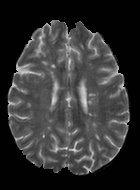

Patch size is another important parameter of the network. In computer vision applications such as object detection, usually a whole 2D image is used as a feature. However, full 3D medical images can not typically be used because of memory limitations. Fig. 4 shows examples of lesion memberships obtained with different sized 2D patches. As the patch sizes increases, the false positives that are mostly observed in the cortex tend to decrease. Fig. 5 shows a plot of Dice and LFPR with various patch sizes, ordered from left to right according to their increasing size. Note that smaller patches ( to ) produced significantly lower Dice and higher LFPR compared to other patches (), as seen from the memberships in Fig. 4. Also some of the highest Dice and lowest LFPR were observed for patches with large in-plane size, i.e., , , and . It was observed in Fig. 5 that there is no significant difference between Dice coefficients for , , or , but LFPR of both and are significantly lower than that of (). We chose as the optimal patch size. Other choices of smaller and patches (not shown) yielded worse results. Note that although training was performed with different patch sizes, the memberships were generated slice by slice, as the trained model consisted only of convolutions and did not need any information about patch sizes.